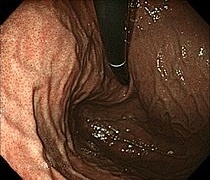

早期胃がん

(NBI画像)